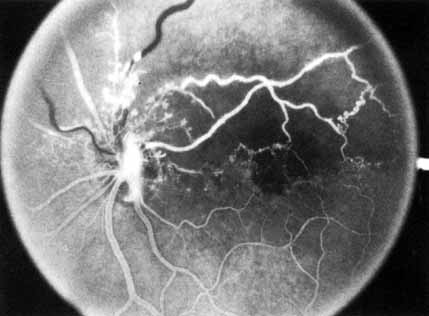

Fig. 1 A. “Blood and thunder” appearance of a central retinal vein occlusion. B. Intravenous fluorescein angiogram shows this occlusion is primarily ischemic or nonperfused. The fact that there is more nonperfusion in the inferior half of the fundus compared with the superior half is unusual.

Coats55 may have been the first to suggest that patients with central retinal vein occlusion fall into two groups: one with a dramatic, “blood and thunder” ophthalmoscopic appearance, loss of vision, and a poor prognosis (see Fig. 1); and the other with mild ophthalmoscopic changes, generally good visual acuity, and a relatively good prognosis (Fig. 2). Other investigators have commented on the difference in severity among central retinal vein occlusions, relying principally on the fluorescein angiogram to assess the severity of occlusion.56–59

The intravenous fluorescein angiogram pattern of an ischemic central retinal vein occlusion is usually characterized by a delayed filling time of the venous tree of the retina, capillary and venous dilation, and extensive leaking of fluorescein into the retina, particularly in the macular area and in the area adjacent to the larger venous trunks and capillary nonperfusion (see Fig. 3C and 3D; Figs. 4 and 5). Microaneurysms may not be noted at the time of initial occlusion, but are usually manifest shortly thereafter. Late-phase photographs show patchy extravascular areas of fluorescence and staining of the retinal veins. Fluorescence in the macula indicates capillary leakage and edema; this not only may account for much of the initial visual loss in the acute phase, but may also eventually result in permanent structural changes. Intravenous indocyanine green videoangiography may also be helpful in showing the arterial and venous flow alterations in this condition.322

Fig. 4 Fluorescein angiogram after moderately ischemic central retinal vein occlusion. A. Early venous phase. The capillary bed is dilated and engorged. Punctate areas of fluorescence represent microaneurysms or small areas of capillary leakage. B. Midvenous phase. There is considerable delay in venous return and an increase in and coalescence of punctate areas of extravascular fluorescence. C. Late venous phase. Fluorescence staining along the vein margins and scattered areas of capillary nonperfusion (arrow) are present.

Fig. 5 Fluorescein angiogram of acute ischemic retinal vein occlusion. Capillary nonperfusion is essentially 100%.